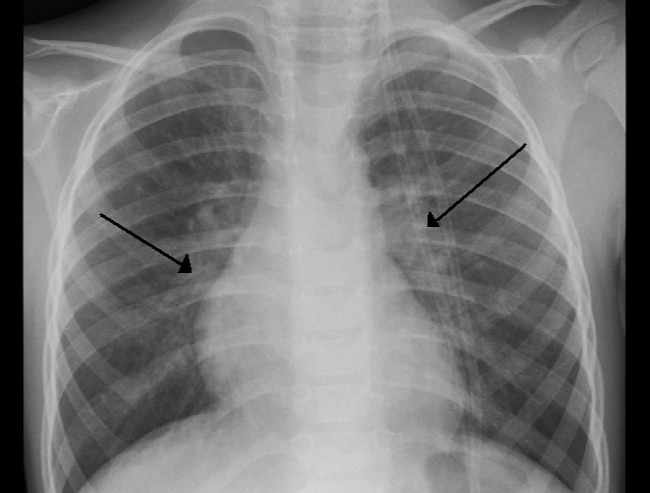

Diagnosis bronkiolitis dibuat berdasarkan usia, takipnea, dan adanya hidung tersumbat. Pada auskultasi, dapat ditemukan suara nafas rales, wheezing, atau kedua-duanya. Gejala hipoksia, dianggap sebagai penanda perburukan penyakit ini. Hipoksia dapat ditandai dengan takipnea, yaitu frekuensi napas di atas 50 kali/menit.[3]